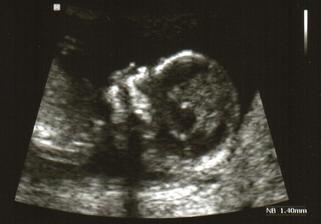

... NT screening ... v pořádku, krevní testy ukázkové, takže nemusíme na plodovku 🙂 , miminko má 7cm